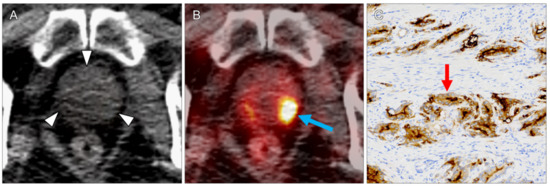

| 1 | mediastinal lymph node | 1.8 | 1.2 | 5.9 | 4.4 | 7.4 | 2 | ccRCC | 2 | 2 | 3 | 2 |

| 10 | right adrenal gland | 1.2 | 0.9 | 7.7 | 4.9 | 7.7 | 2 | ccRCC | 3 | 3 | 3 | 3 |